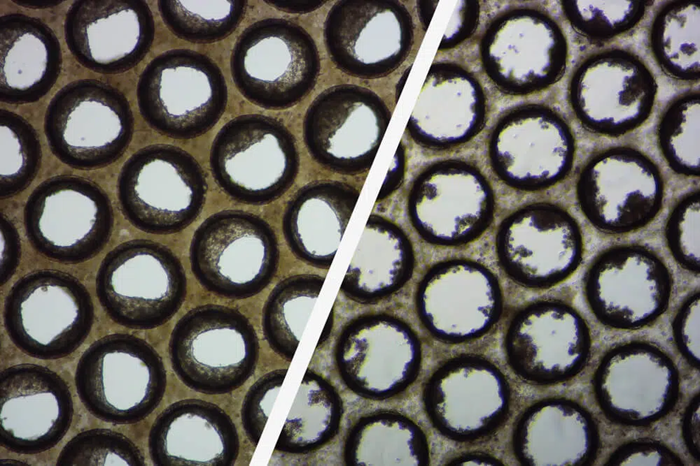

Good/poor liver microtissue. Image Credit: CN-Bio

Image Credit: CN-Bio

These brightfield pictures show how the pores of individual Multi-chip Liver-12 plate scaffolds form good (left) and poor (right) liver microtissue formation.